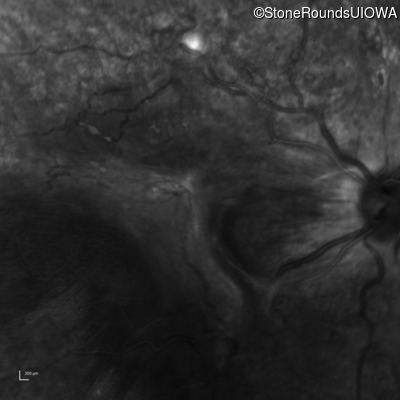

Infrared Fundus Photograph - Right - 20/400 sc

Exemplar

Infrared Fundus Photograph - Left - 20/250 sc